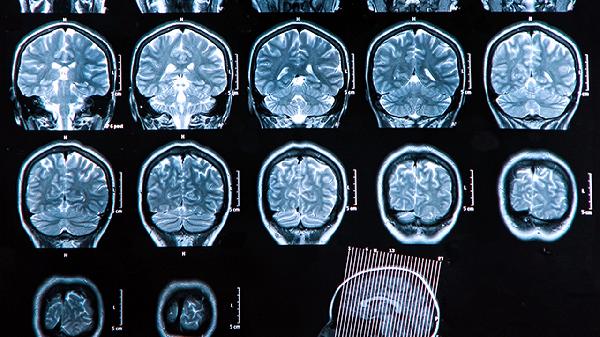

一、过度疲劳是如何摧毁血管的?

当身体长期处于超负荷状态,交感神经会持续兴奋,好比让汽车发动机始终处于红线转速。血管内皮细胞在这种高压下逐渐受损,为日后破裂埋下隐患。

熬夜时人体分泌的压力激素激增,血压如同过山车般剧烈波动。脆弱的脑血管可能在没有明显征兆的情况下突然崩盘,这种情况在临床并不罕见。